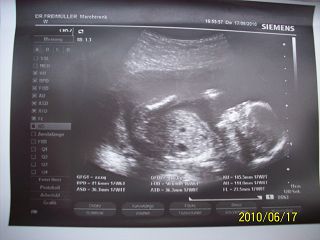

éééés, tegnap voltam uh-n. :) sziszka, most már nálunk is biztos, kisfiú lesz, neve pedig Levente. :) most már nem csak tippelték a nemét, szépen megmutatta mije is van. Egyébként meg szégyenlős volt, teljesen be volt fordulva, szopizta az ujját. de a kis kukacát persze megmutogatta nekünk. :)

ja igen a méretei: 153 g. bpd: 40,8 mm, ac 106 mm. 17+3nak felel meg. picit belehúzott. :)